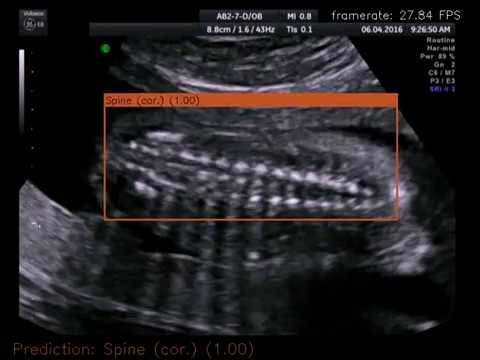

Demo videos are available on Youtube: